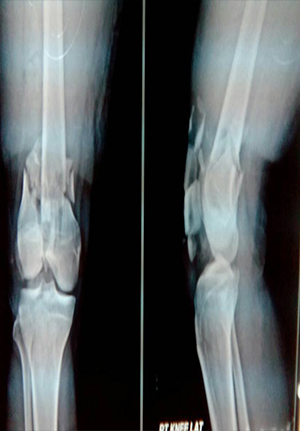

Pre and post op picture of comminuted fracture distal femur and patella in RTA

before operation